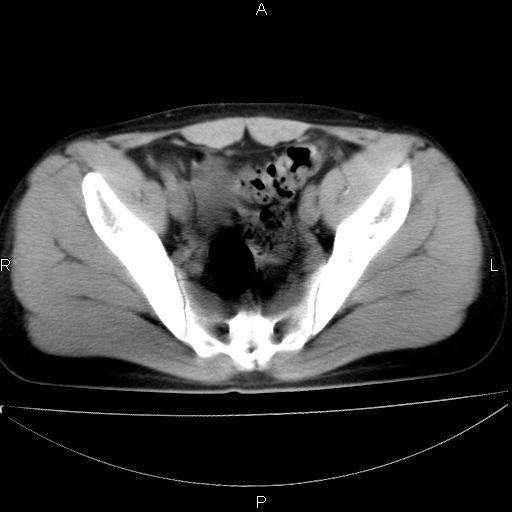

男 25岁 自述 尿频尿急,排尿困难20多天.无腰痛, b超说左肾盂轻度积水,左输尿管上端扩张.未见结石影. ct我看双侧肾盂轻度积水,双输尿管上端都扩张,大家看看能看见结石吗?

正常变异。

考虑肾外肾盂 前列腺轻度肿大 密度欠均 考虑炎性改变

肾外肾盂,必要时+c